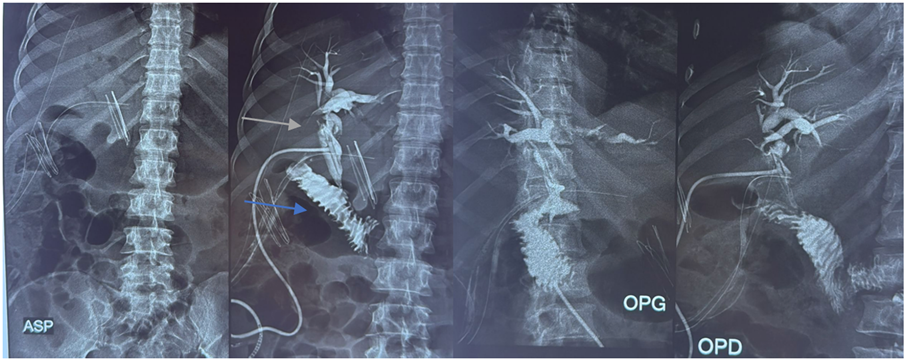

T-tube Cholangiography

No calcified opacity was identified projecting over the hepatic area. Surgical drainage tubes were visualized in the subhepatic region. Digestive gas was present.

Following opacification with iodinated contrast medium injected through the Kehr T-tube, the T-tube was confirmed to be in place. Mild dilatation of the proximal right and left intrahepatic bile ducts was observed, containing a few filling defects consistent with aerobilia. There was slight dilatation of the common bile duct, without any clearly identifiable obstructive lesion. The gallbladder and cystic duct were not visualized. Contrast medium passed freely into the duodenum, with no evidence of contrast extravasation.

Figure 4: T-tube cholangiography demonstrating adequate opacification of the biliary tree with free passage of contrast into the duodenum, but without visualization of the gallbladder. Dilated common bile duct with visualization of the Kehr T-tube (green arrow) and the duodenum (blue arrow).